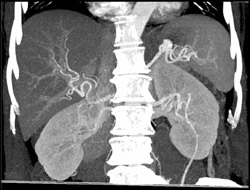

Diagnosis

Patent SMV/PV